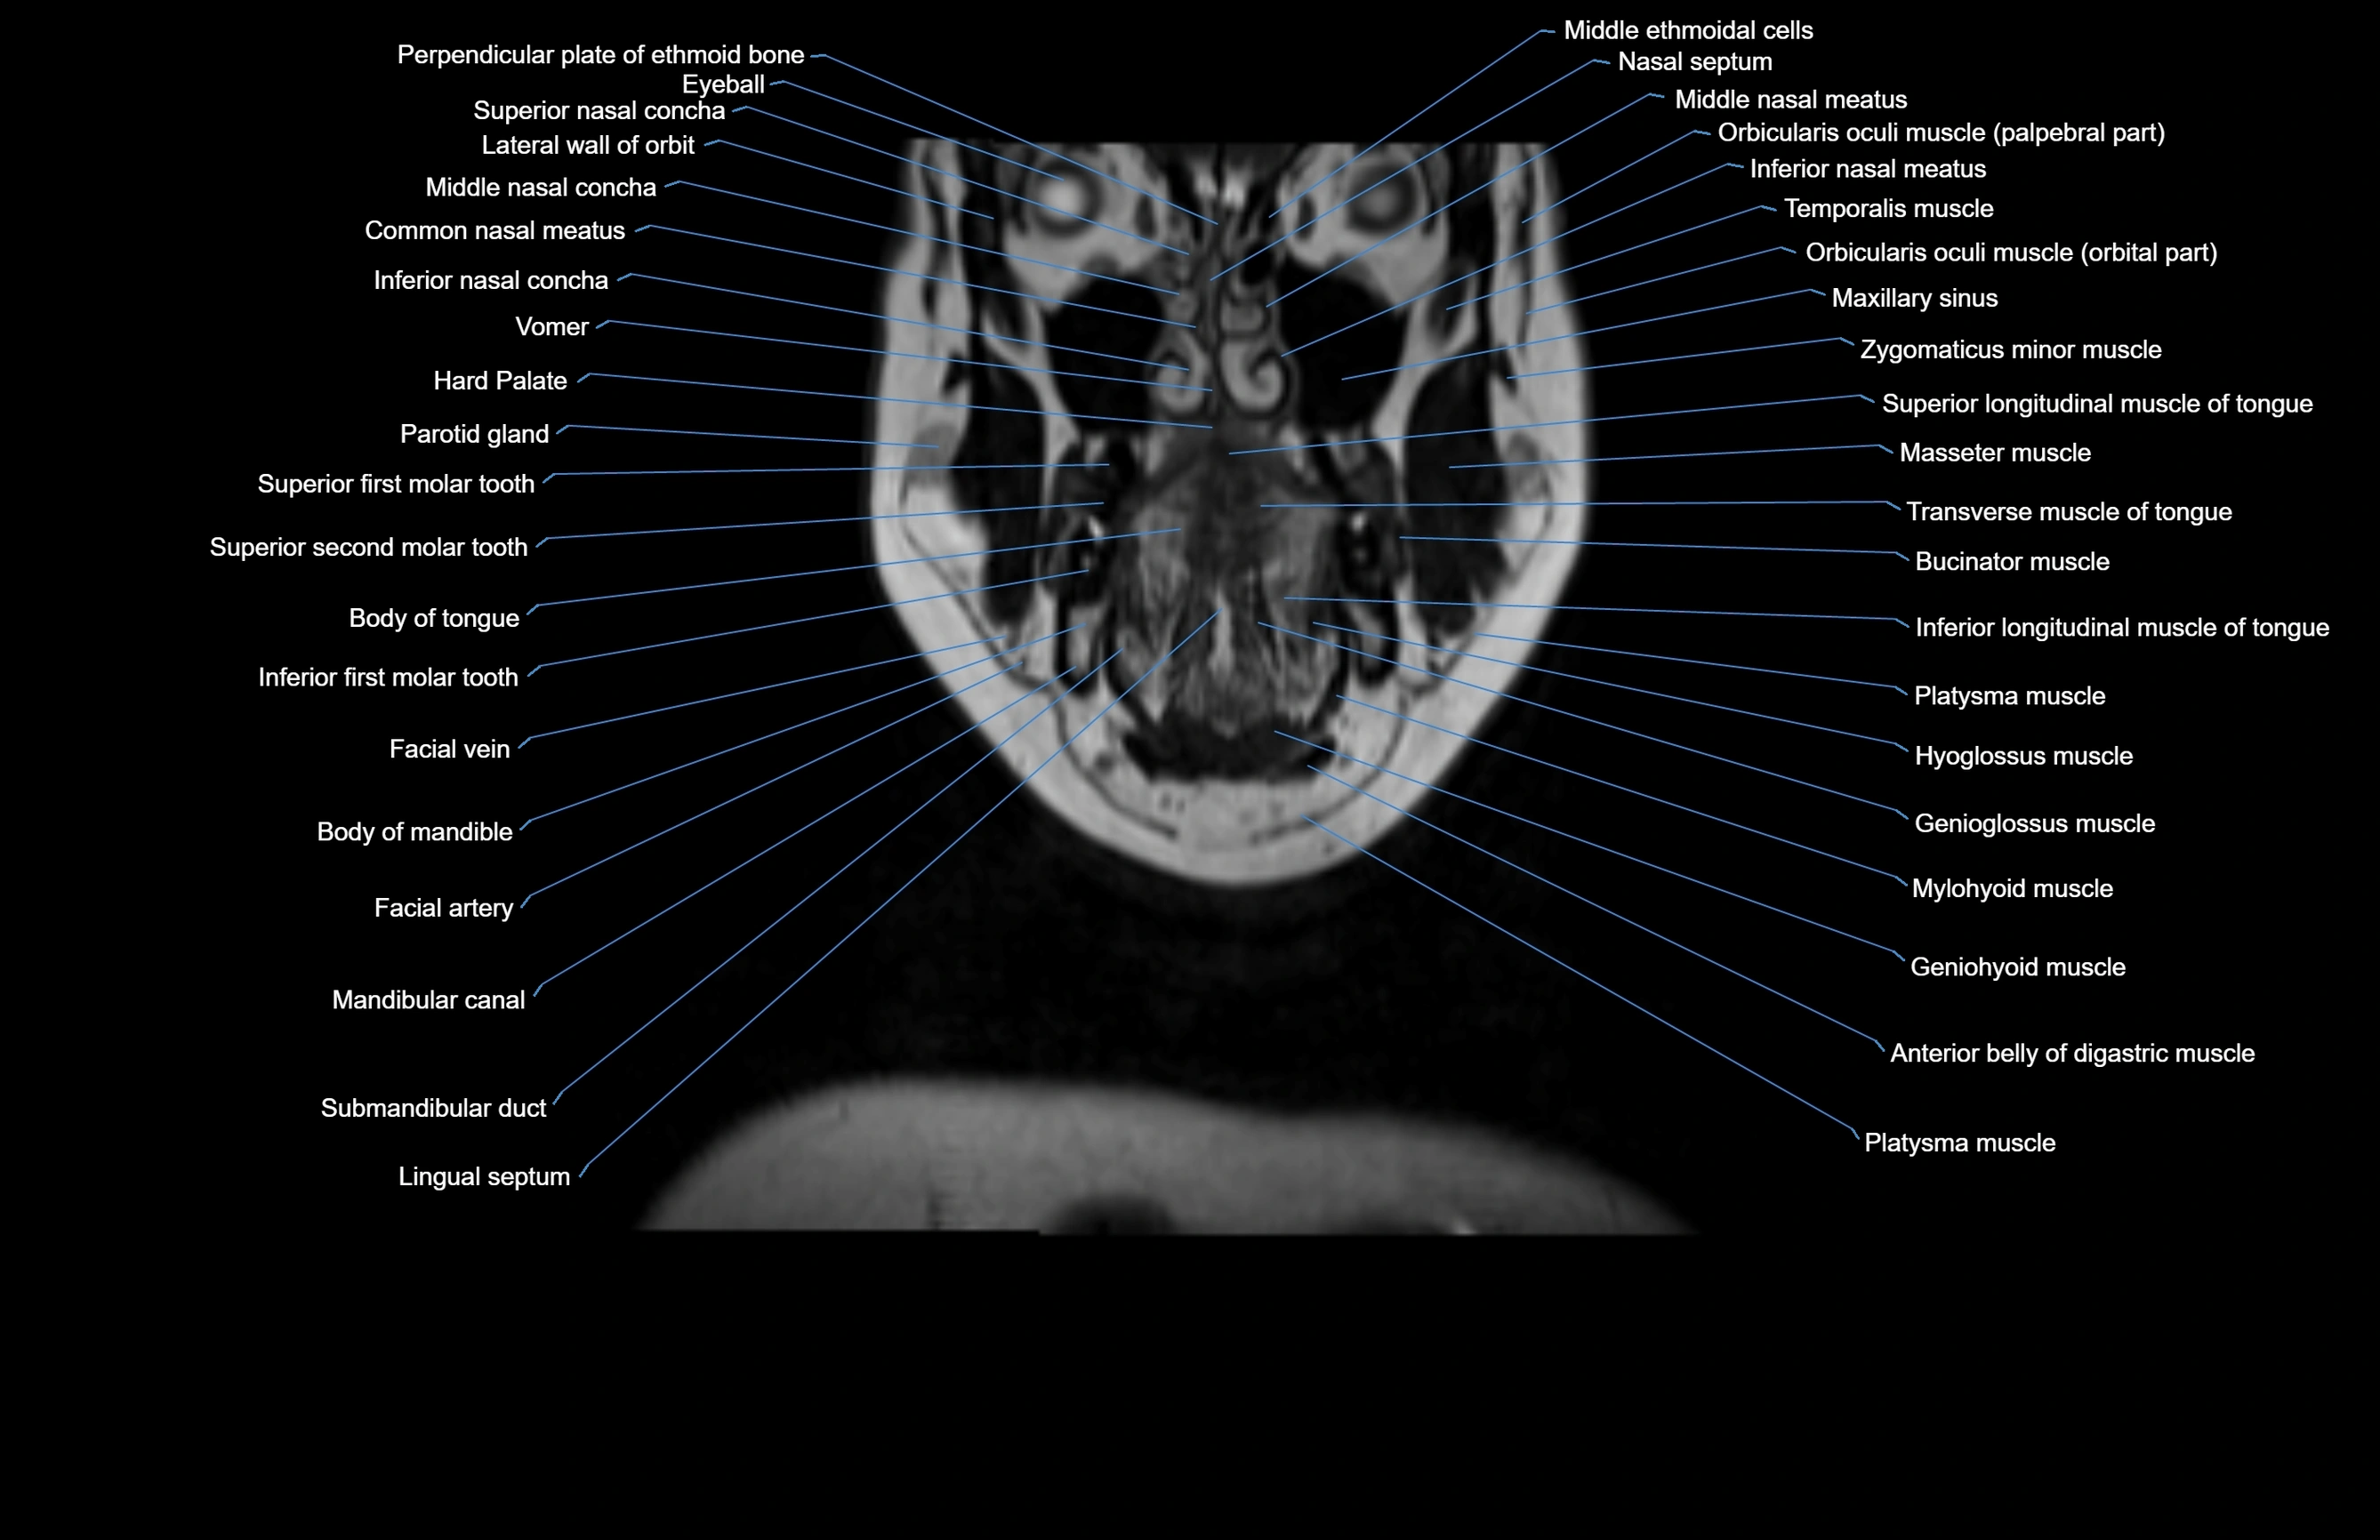

MRI images